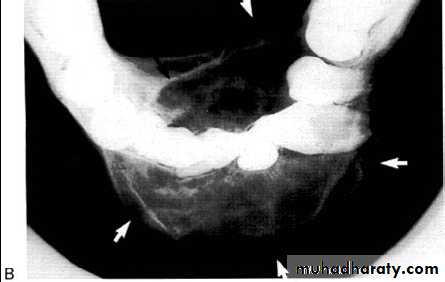

Multilocular appearance, expansion (arrowed) and considerable displacement of the adjacent teeth.

Buccal and lingual expansion (arrowed) and the undulating cortical border.